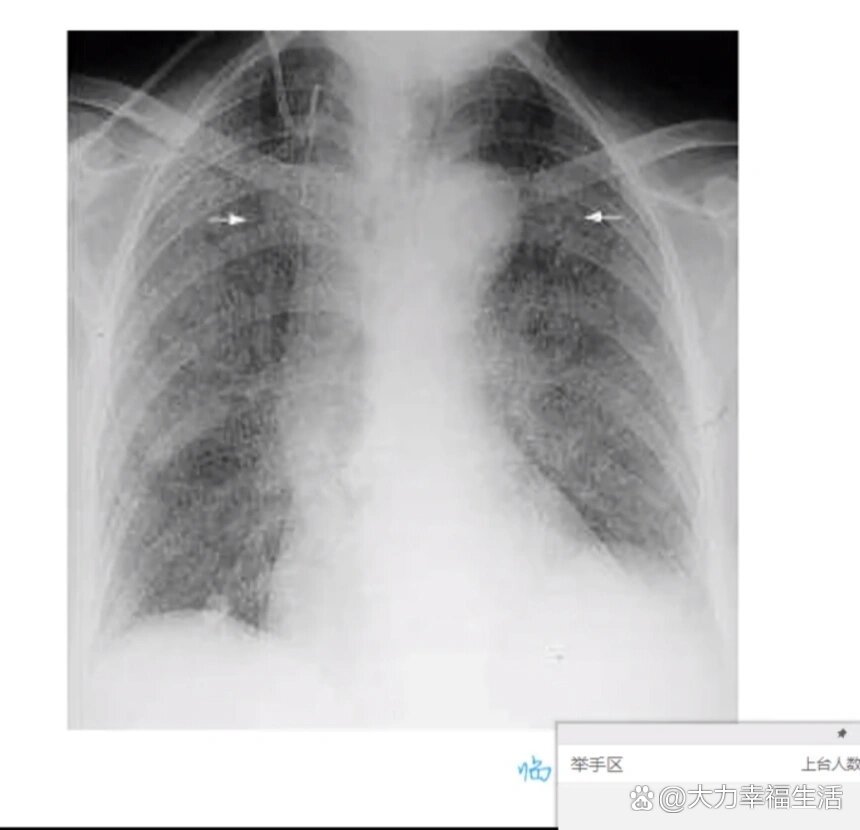

肺结核的影像学表现及鉴别诊断

肺结核的影像学表现及鉴别诊断

肺结核的影像学表现及鉴别诊断

肺结核的影像学表现及鉴别诊断

肺结核的影像学表现及鉴别诊断

肺结核的分型及影像学表现

肺结核的影像学表现及鉴别诊断